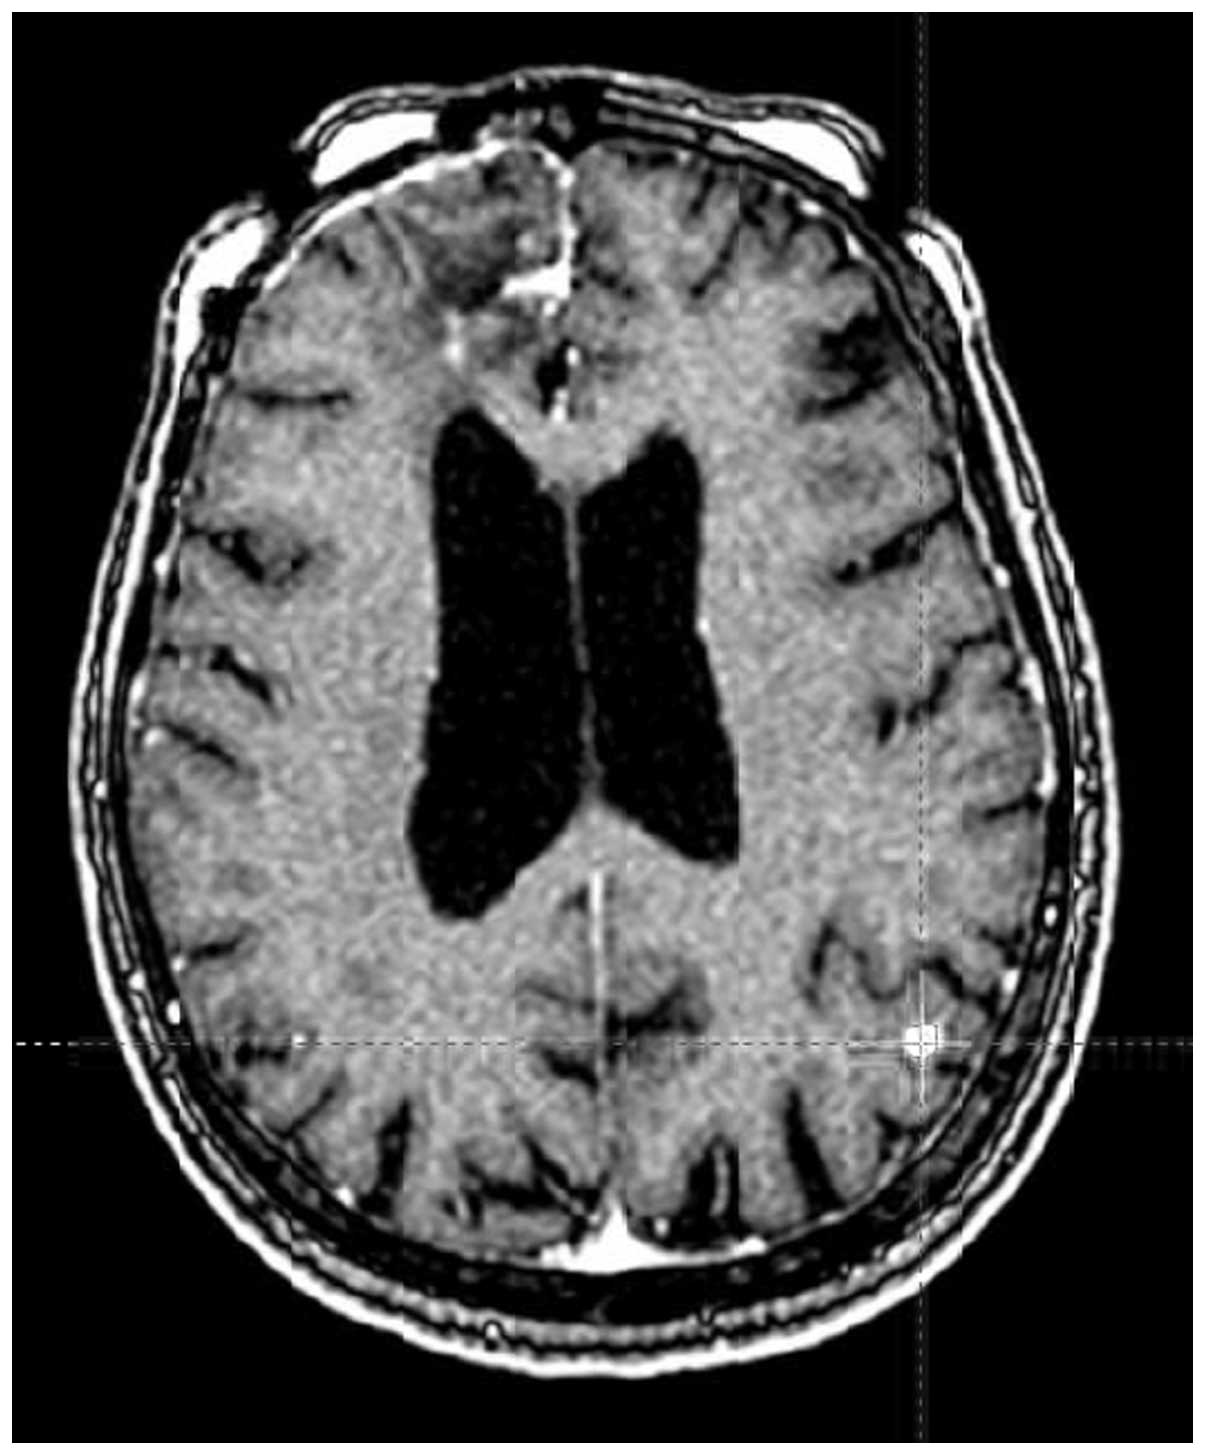

Brain metastases management paradigm shift: A case report and review of the literature

Brain metastases are the most common intracranial tumors in adults, accounting for over half of all lesions. Whole‑brain radiation therapy (WBRT) has been a cornerstone in the management of brain metastases for decades. Recently, stereotactic radiosurgery (SRS) has been considered as a definitive or postoperative approach instead of WBRT, to minimize the risk of cognitive impairment that may be associated with WBRT. This is the case report of a 74‑year‑old female patient who was diagnosed with lung cancer in November, 2002, and histopathologically confirmed brain metastases in January, 2005. The patient received 5 treatments with Gamma Knife SRS for recurring brain metastases between 2005 and 2014. The patient remains highly functional, with stable intracranial disease at 10 years since first developing brain metastases, and with stable lung disease. Therefore, Gamma Knife SRS is a safe and effective treatment modality for patients with recurrent intracranial metastases, with durable local control and minimal cognitive impairment.

Figure 1

Figure 2

Figure 3